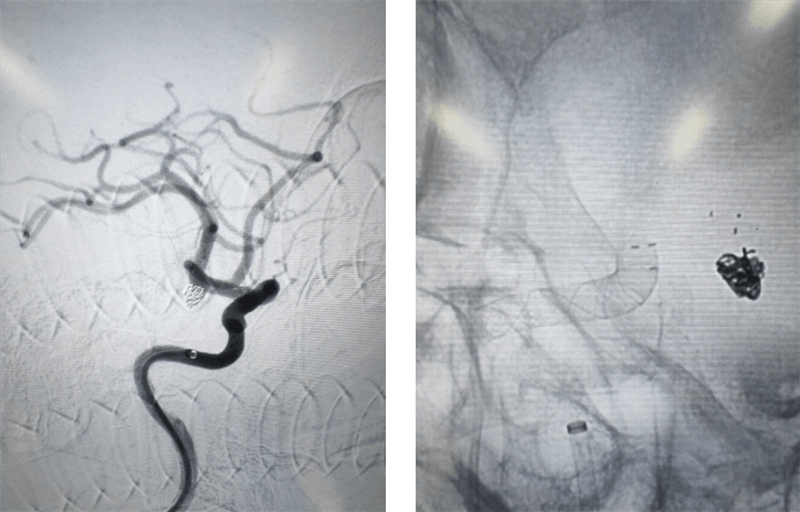

(术前3D造影)

术中,介入团队对患者右侧颈内动脉末端两枚动脉瘤采用密网支架覆盖,左侧脉内动脉末端动脉瘤采用弹簧圈填塞。在手术过程中,对患者左侧颈内动脉使用6F长鞘,6F中间导管建立通路 ,分别使用X17 与headway-17微导管输送Atlas辅助支架和数枚弹簧圈完成填塞。右侧颈内动脉使用导引导管 GC-088-09 颅内支撑导管同轴,在导丝引导下,将远端通路导管DA6115ST至右侧颈内动脉海绵窦段。选择合适工作角度,沿神经血管导丝TNGW-14-200-S将TJMC18 Plus微导管送至大脑中动脉,沿TJMC18 Plus送入NUVA 4.5*25mm血流导向密网支架, 支架顺利打开。支架释放后造影可见支架显影清晰,形态良好,无贴壁不良。支架释放后观察10分钟,无异常。经过几个小时的奋战,手术终于顺利结束,患者重获健康。

术后影像